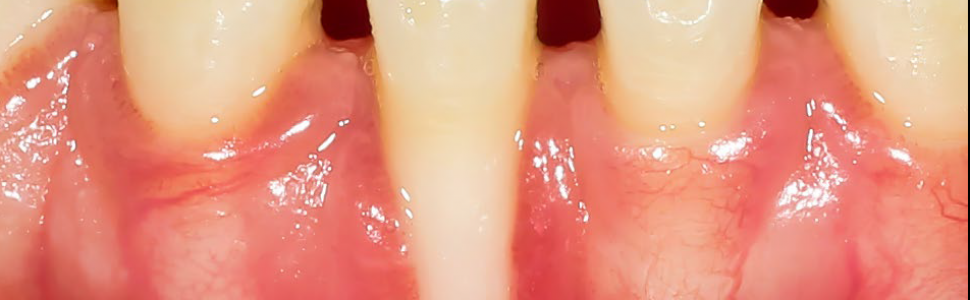

Wynik kliniczny zabiegu był zadowalający – ulegał ciągłej poprawie obserwowanej po trzech dniach, następnie po pierwszym tygodniu i po drugim tygodniu od zabiegu.

Badania kliniczne wskazują na to, że połączone techniki dokoronowo przemieszczonego płata z wolnym przeszczepem nabłonkowo-łącznotkankowym błony śluzowej pozwalają osiągnąć sukces w pokrywaniu odsłoniętej powierzchni korzenia w 70-90%. Kolejne badania dowiodły, że połączenie techniki zrotowanej brodawki z dokoronowo przemieszczonym płatem w pokrywaniu recesji o wielkości od 2 do 4 mm zapewnia znaczne pokrycie korzenia zęba oraz zadowalający, naturalny efekt kosmetyczny.

Połączenie techniki dokoronowo przemieszczonego płata z wolnym przeszczepem nabłonkowo-łącznotkankowym błony śluzowej pozostaje jedną z bardziej efektywnych metod leczenia recesji dziąsłowych. Proces gojenia zachodzi sprawnie dzięki bogatemu ukrwieniu przeszczepu, co prowadzi do jego pełnej integracji z miejscem biorczym. Wyniki przeprowadzonych zabiegów z użyciem opisanej techniki wskazują na jej niezawodność w pokrywaniu powierzchni korzeni z pozytywnym efektem kosmetycznym – przekłada się to na ogólny dobrostan przyzębia.